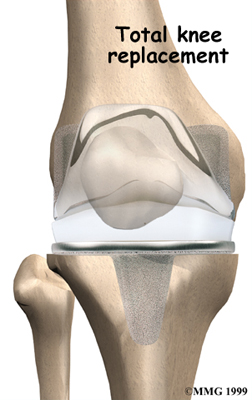

Artificial Knee Replacement

An artificial knee replacement is the ultimate solution for advanced knee OA.

Surgeons prefer not to put a new knee joint in patients younger than 60. This is because younger patients are generally more active and might put too much stress on the joint, causing it to loosen or even crack. A revision surgery to replace a damaged prosthesis is harder to do, has more possible complications, and is usually less successful than a first-time joint replacement surgery.

Related Document: FYZICAL Northwest Tucson's Guide to Artificial Joint Replacement of the Knee